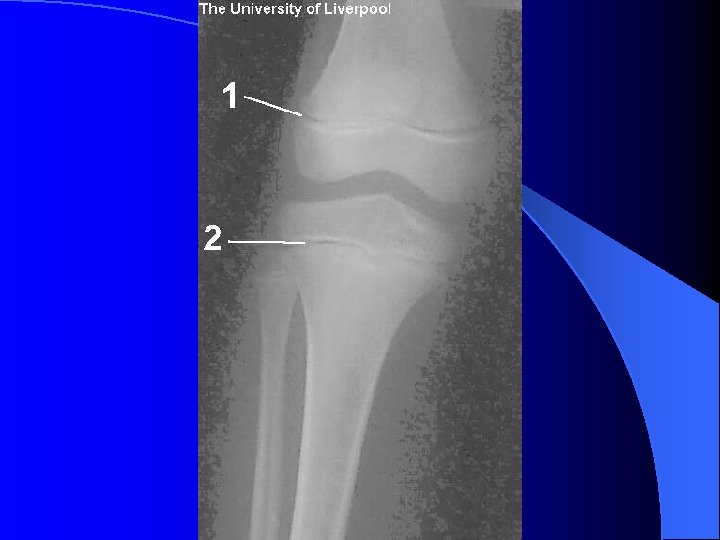

Structure of Long Bone l Epiphyses – Expanded ends of long bones – Exterior is compact bone, and the interior is spongy bone – Joint surface is covered with articular (hyaline) cartilage – Epiphyseal line separates the diaphysis from the epiphyses

Structure of Long Bone Figure 6. 3 a, b